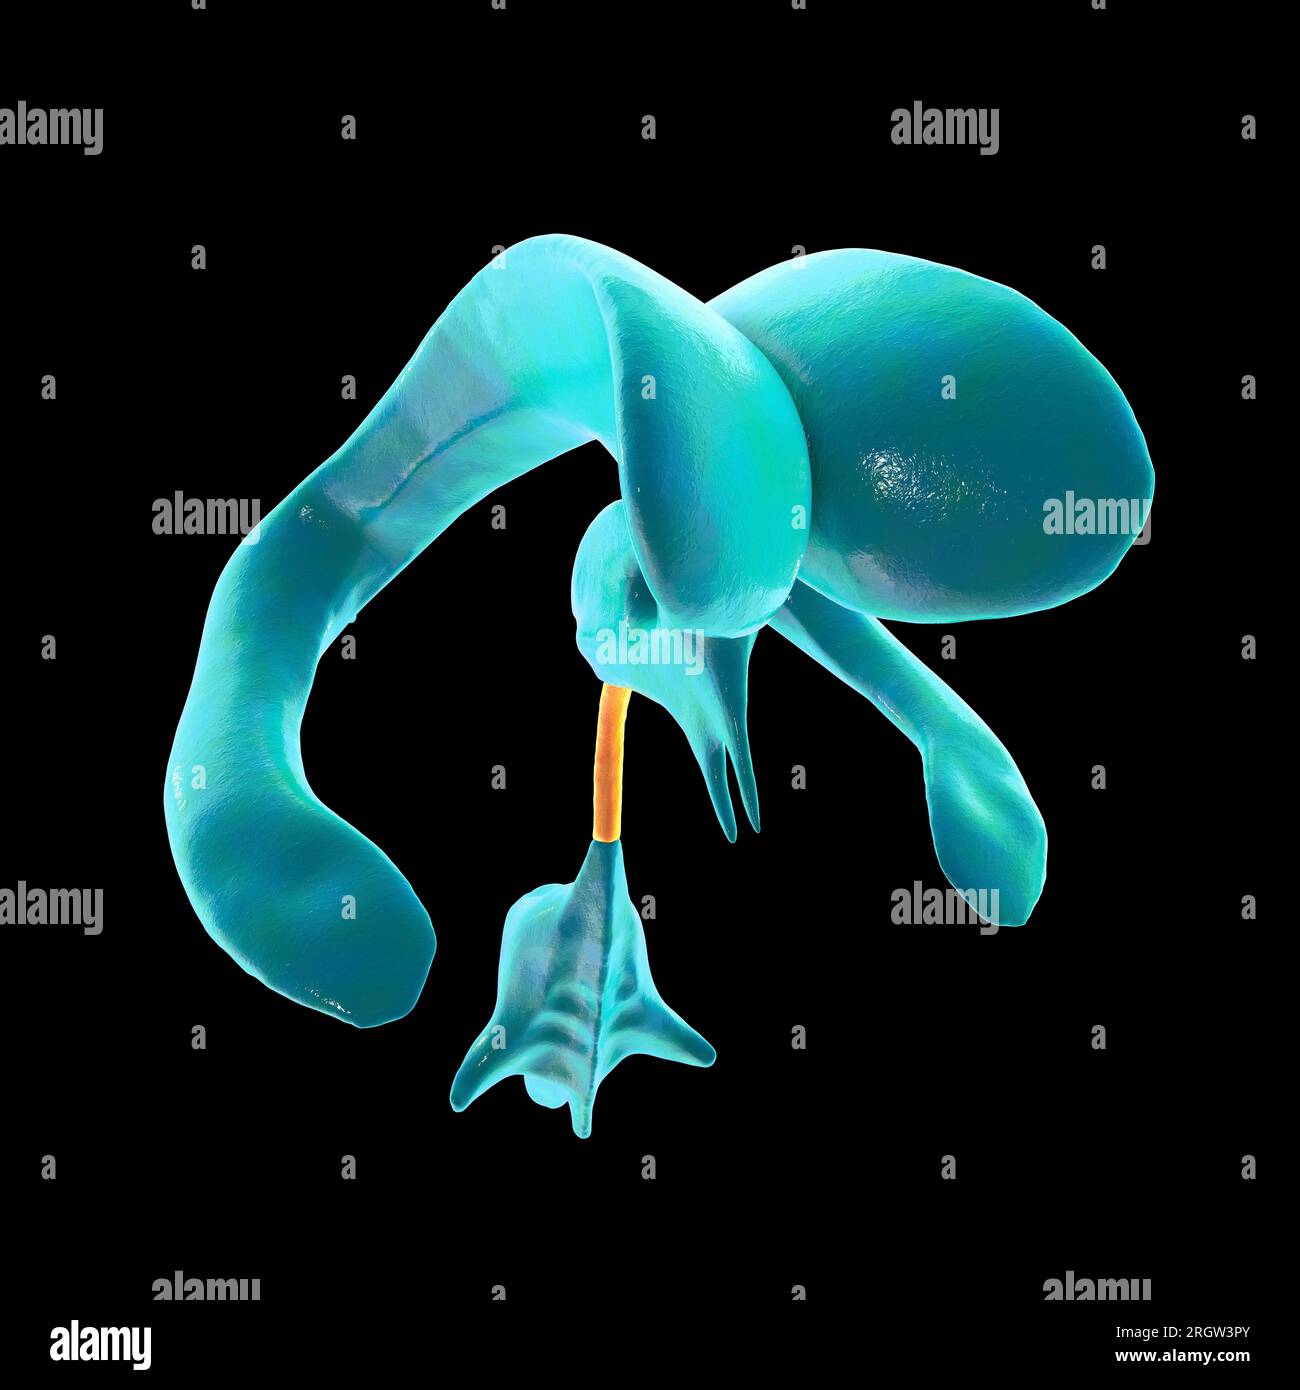

RF2T030FH–Röntgenprofilansicht des Sylvius oder des zentralen Aquädukts des Gehirns 3D-Rendering-Illustration. Menschliche Körperanatomie, Medizin, Biologie, Wissenschaft, Neurowissenschaft,

RF2T6AR8J–3D-Rendering-Illustration für die Röntgenansicht des Gehirns oder des Sylvius aquädukt. Anatomie des menschlichen Gehirns und des Ventrikelsystems, Medizin, Gesundheitswesen, Biologie, Wissenschaft,